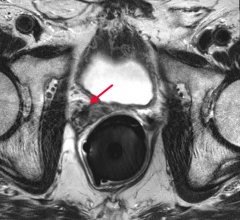

While prostate cancer is one of the most common cancers among American men — the third leading cause of cancer deaths in ...

Prostate Cancer

News and new technology innovations concerning how imaging technology can help diagnose and treat prostate cancer can be found on this channel.